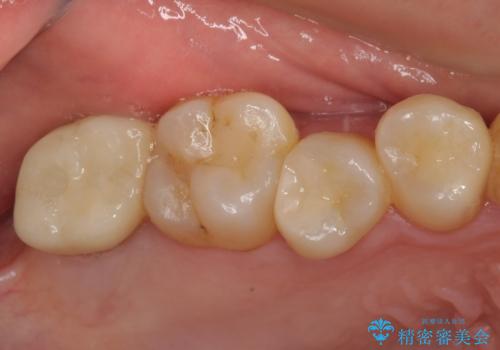

痛みのある歯が多く、根管治療が必要と診断されました。

根管治療や歯周外科処置後にフルジルコニアクラウンにて補綴治療することとしました。